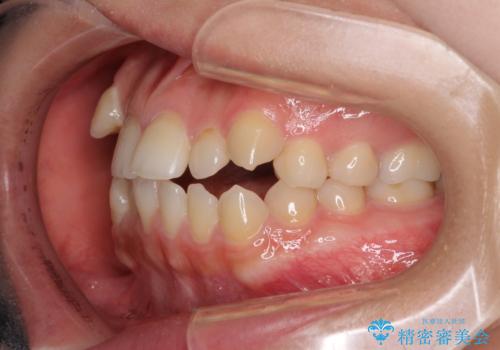

- 前歯のデコボコや八重歯、舌癖による開咬を気にして来院された患者様です。

目立たない装置を希望されたので、上顎が裏側装置のハーフリンガルを選択し、上顎小臼歯1本を抜歯して、補助装置を併用して矯正治療を行うこととしました。